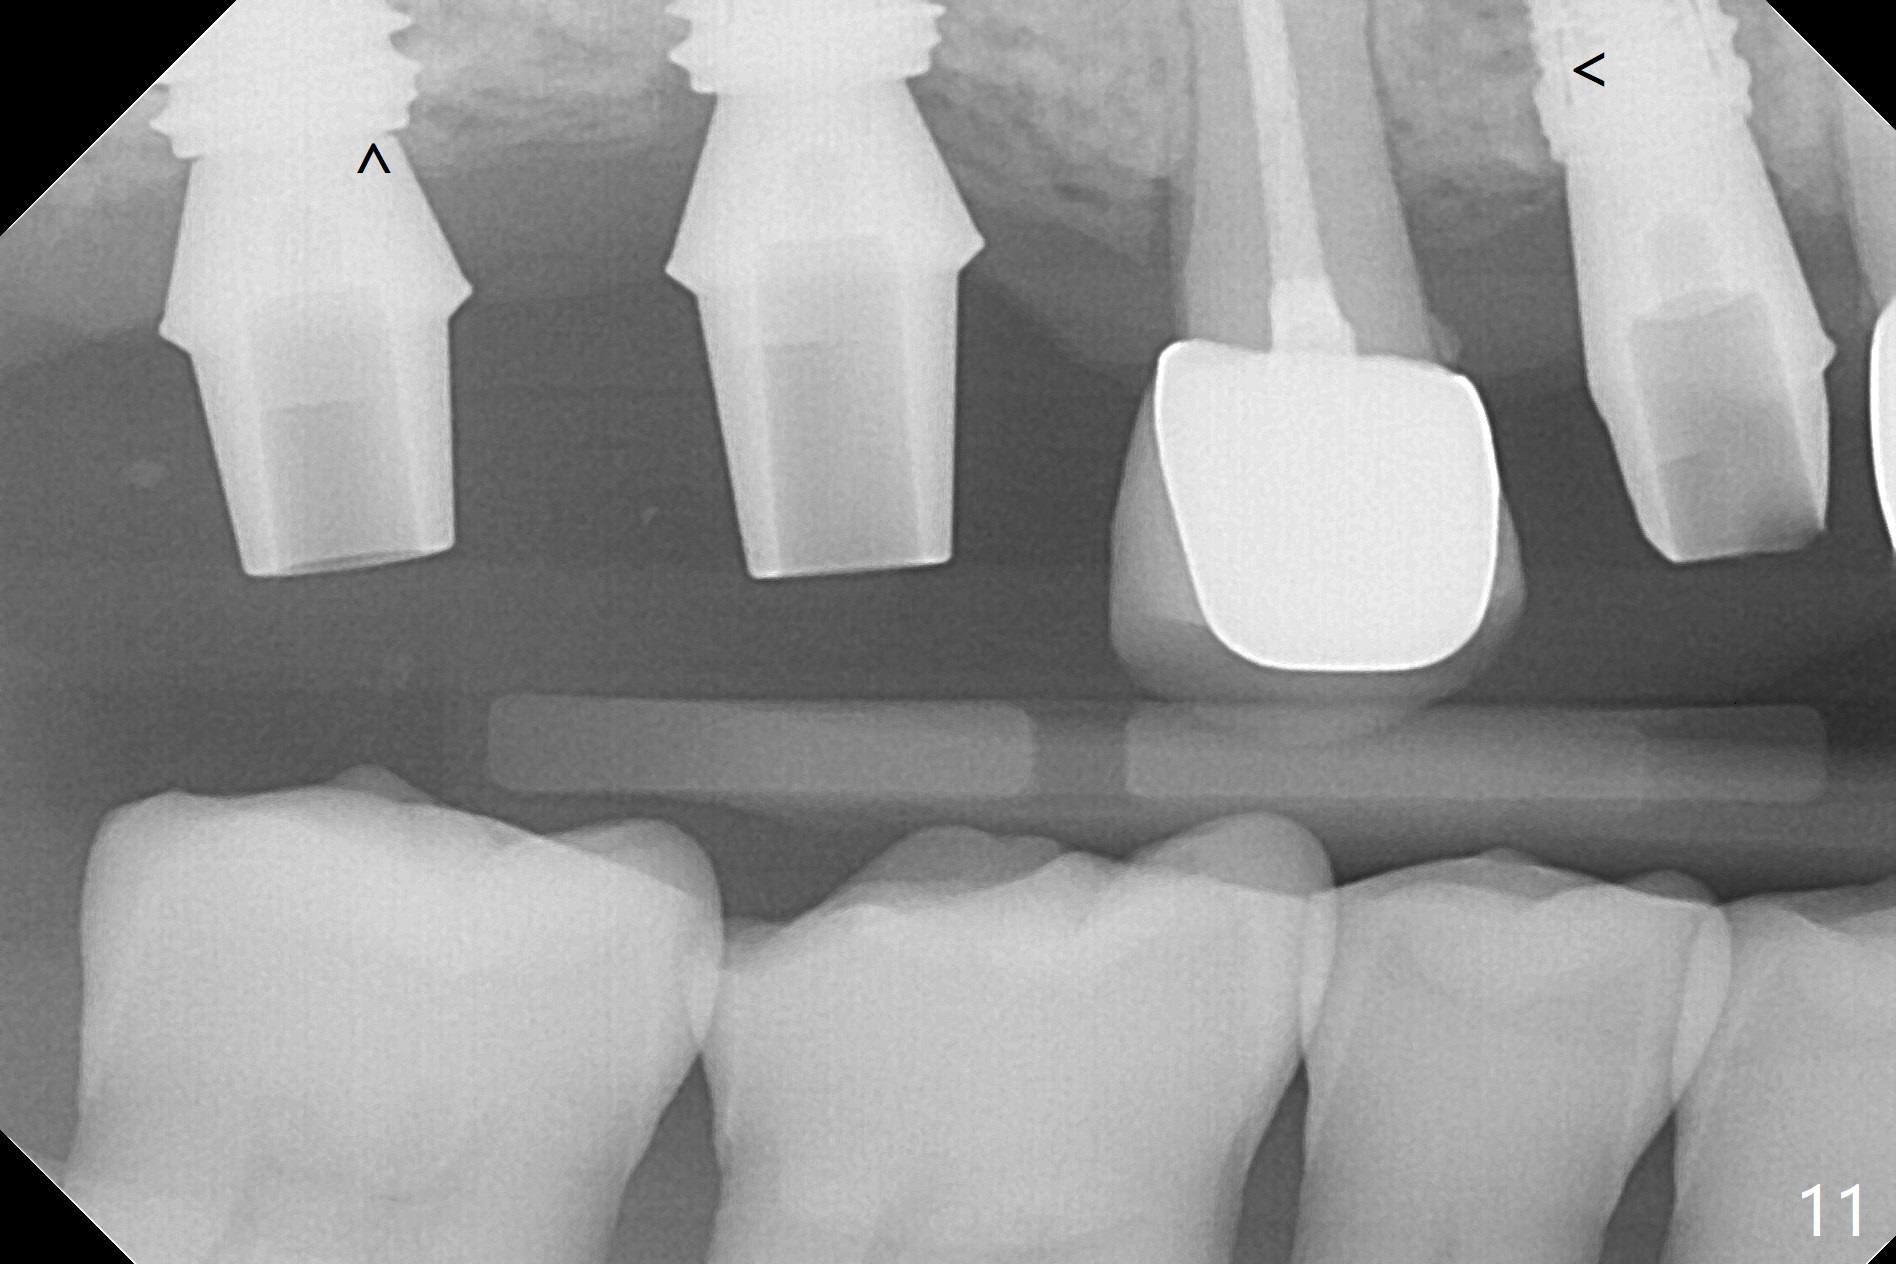

Two of 5x8.5 mm implants are placed at #2 and 3 with sinus lift using water ballooning technique; to avoid invading the neighboring root tips, an intraop PA is taken with a 2.2x11.5 mm drill at #5 (Fig.1). When a 2.5x11.5 mm 1-piece implant is placed at #7, there is 2.4 mm clearance from the impacted tooth (Fig.2). Following 1 mm deeper placement of the 1-piece implant, CT is taken to make sure that the threads are completely covered palatally (Fig.5 P). Interesting is that the sinus membrane is thickened at #2 and 3 (Fig.3 M), as compared to the clear sinus before surgery (Fig.3'). Bone graft is limited in the sinus (Fig.3 arrowheads). The implant at #5 (3.5x11.5 mm) is precisely placed subcrest bucco(B)-palatally (Fig.4). Since the limited field viewed CT does not cover the implant at #2 (Fig.3), immediate postop PA is taken (Fig.6). In fact all of the implants are placed subcrestal, as shown by intraoral X-ray 4 months postop (Fig.7-9). The abutments at #2, 3 and 5 are retorqued (30 Ncm) after crowns' try in and adjustment (Fig.10,11). There is a vertical gap between the implant and abutment at #2 (Fig.11 ^) and a horizontal one at #5 (<). There is apparently no bone loss 1 year 5 months post cementation (Fig.12).